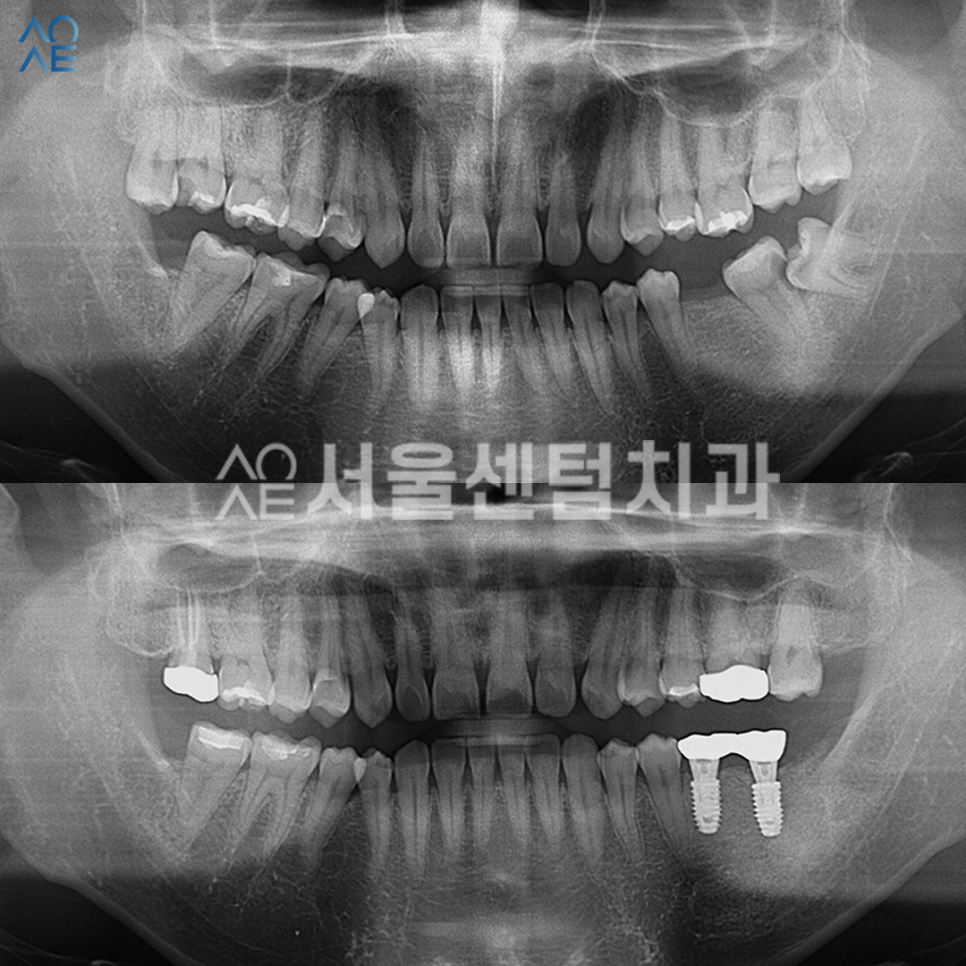

전/후 비교 이미지를 보시면

깔끔하게 잘 마무리 된 모습을 확인할 수 있습니다.

이제 왼쪽 아래에 임플란트까지 식립 후

촬영한 엑스레이입니다.

2개 모두 일체형으로 식립했기 때문에

2차수술은 필요하지 않았고

잇몸이 충분히 아무는 시간을 가지도록 했습니다.

임플란트까지 완성된 모습입니다.

이 분의 경우엔 잇몸뼈가 충분히 있었기에

뼈이식은 진행하지 않았습니다.

식립은 정확한 방향으로 안정적으로 잘 되었고

보철물 수복 역시 문제없이 마무리 되었습니다.